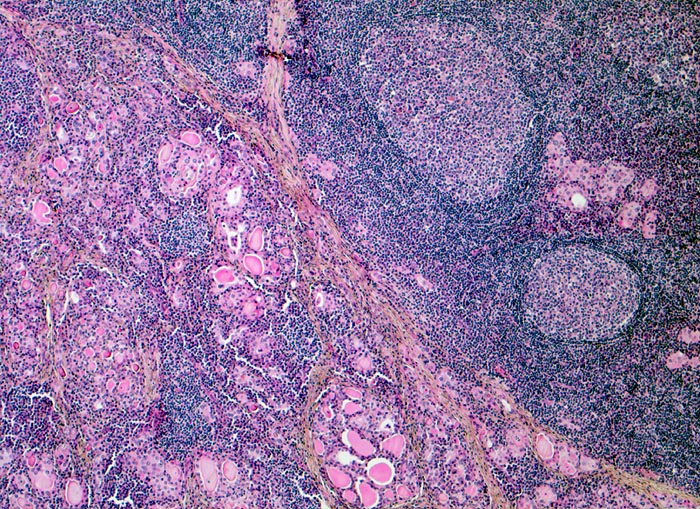

Hashimoto Thyreoiditis

Die zytologische Diagnose einer Hashimoto Thyreoiditis gelingt meist eindeutig. Der Autoimmunprozess ist mit einer chronischen Entzündung verbunden, die zu einer Zerstörung der Schilddrüsenfollikel führt. Das Entzündungsinfiltrat besteht aus Lymphozyten, Plasmazellen, lymphohistiozytären Aggregaten, Sternhimmelmakrophagen und Riesenzellen. Im Hintergrund sind lymphoglanduläre Körperchen zu sehen. Schaumzellen und Makrophagen sind gelegentlich beigemischt. Als Folge der Gewebsdestruktion ist das follikuläre Epithel degeneriert (Kernpyknosen, vakuolisiertes Zytoplasma) oder zeigt eine onkozytäre Metaplasie teilweise mit Atypie. Die Diagnose der Hashimoto Thyreoiditis basiert auf dem Nachweis von chronischer Entzündung und Onkozyten.